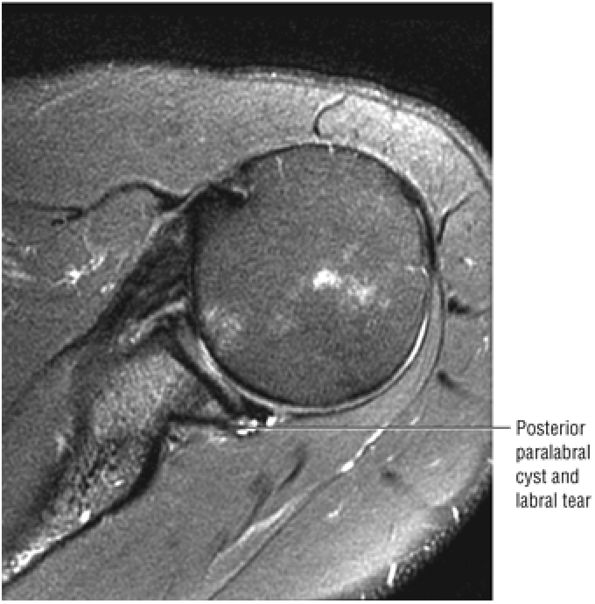

Axial FS PD FSE images are sensitive for the detection of small paralabral cysts as markers for labral tears.

A separate FS PD-weighted FSE sequence is used to increase sensitivity to fluid and to identify paralabral cysts, articular cartilage labral avulsions, and muscle edema (Fig. 8.4). FSE sequences are less sensitive to intralabral signal intensity in the spectrum of degenerations or tears unless there is imbibed fluid. FSE (FS PD FSE) images, however, are superior for the demonstration of labral morphology in cases of avulsions or contour abnormalities.